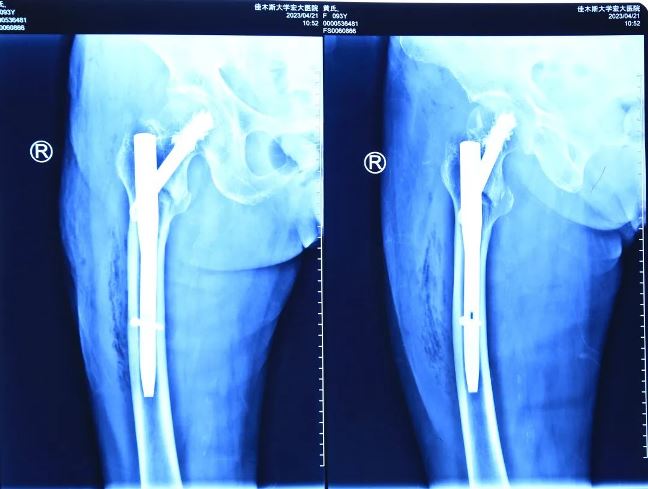

術(shù)后影像

秉著視患者如親人的態(tài)度,向患者家屬詳細(xì)解釋了病情以及并發(fā)癥可能性,并告知了高齡體弱患者手術(shù)存在的風(fēng)險(xiǎn)。根據(jù)患者病情,喬院長(zhǎng)建議為患者行右股骨粗隆間骨折閉合復(fù)位髓內(nèi)針內(nèi)固定術(shù)(APFN)。手術(shù)全程僅用不到1小時(shí),手術(shù)過(guò)程安全、無(wú)痛,固定效果良好?;颊咝g(shù)后第二天即可下地活動(dòng),患者的女兒激動(dòng)地說(shuō):“醫(yī)生,謝謝你們!真是太幸運(yùn)了,我母親可以在攙扶下站立走路了,感謝你們,是你們的精湛技術(shù),讓我的家庭再次圓滿”。

隨著醫(yī)療技術(shù)手段及綜合醫(yī)療水平的不斷提高,年齡不再是手術(shù)禁忌證。佳木斯大學(xué)宏大醫(yī)院骨科團(tuán)隊(duì)已成功救治多例85歲以上超高齡粗隆間骨折患者,充分彰顯出醫(yī)院骨科團(tuán)隊(duì)的技術(shù)實(shí)力。目前,對(duì)股骨近端骨折采取APFN髓內(nèi)釘+骨水泥加強(qiáng)固定手術(shù)這一先進(jìn)治療方法,具有手術(shù)操作簡(jiǎn)單、手術(shù)時(shí)間短、固定牢靠、對(duì)骨強(qiáng)度破壞小、出血少、骨折愈合率高等優(yōu)點(diǎn),適合于高齡股骨粗隆間骨折患者的手術(shù)要求,是一種值得推廣的骨科手術(shù)技術(shù)。